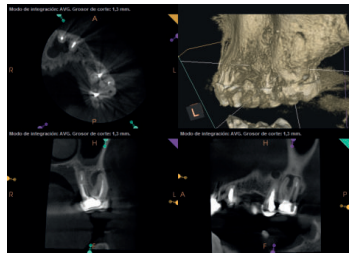

Para confirmar el origen endodóntico y el tamaño de las lesiones se realizaron exploraciones tomográficas con espesor de corte de 75 micras mediante CBCT CS8100 (Carestream Dental® ) en las que se evidenciaron lesiones periapicales radiolúcidas a nivel de 12, 11, 21 (con afectación bicortical), 25 y raíces vestibulares de 26 (Figuras 4 a 8).

Tras la exploración clínica y radiológica mediante radiografías periapicales y tomografía computerizada de haz cónico (CBCT) se decide realizar un abordaje combinado endodóntico-quirúrgico.

El paciente aporta como estudio radiológico una ortopantomografía (OPG), (Figura 1). Se realizaron radiografías periapicales (Figuras 2 y 3), así como exploración clínica incluyendo la valoración periodontal de los dientes afectados, sin observar profundidades de sondaje aumentadas que pudieran indicar la existencia de lesiones endoperiodontales.